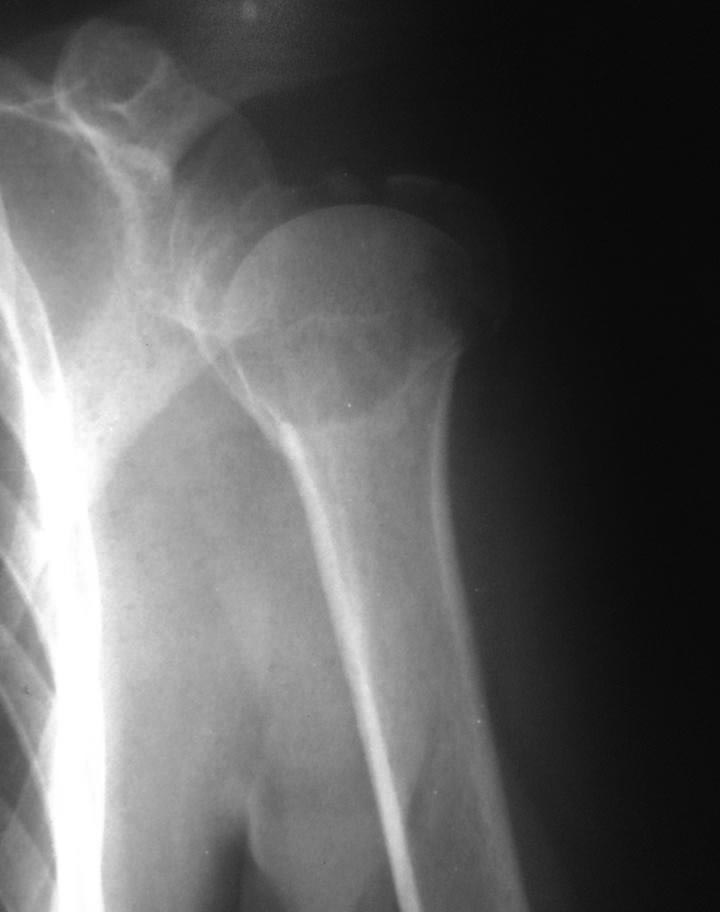

Re: Перелом проксимального метаэпифиза плеча

На снимках плечо вывихнуто. По ркт- открытая репозиция и пластина с угловой стабильностью LCP . Все просто.